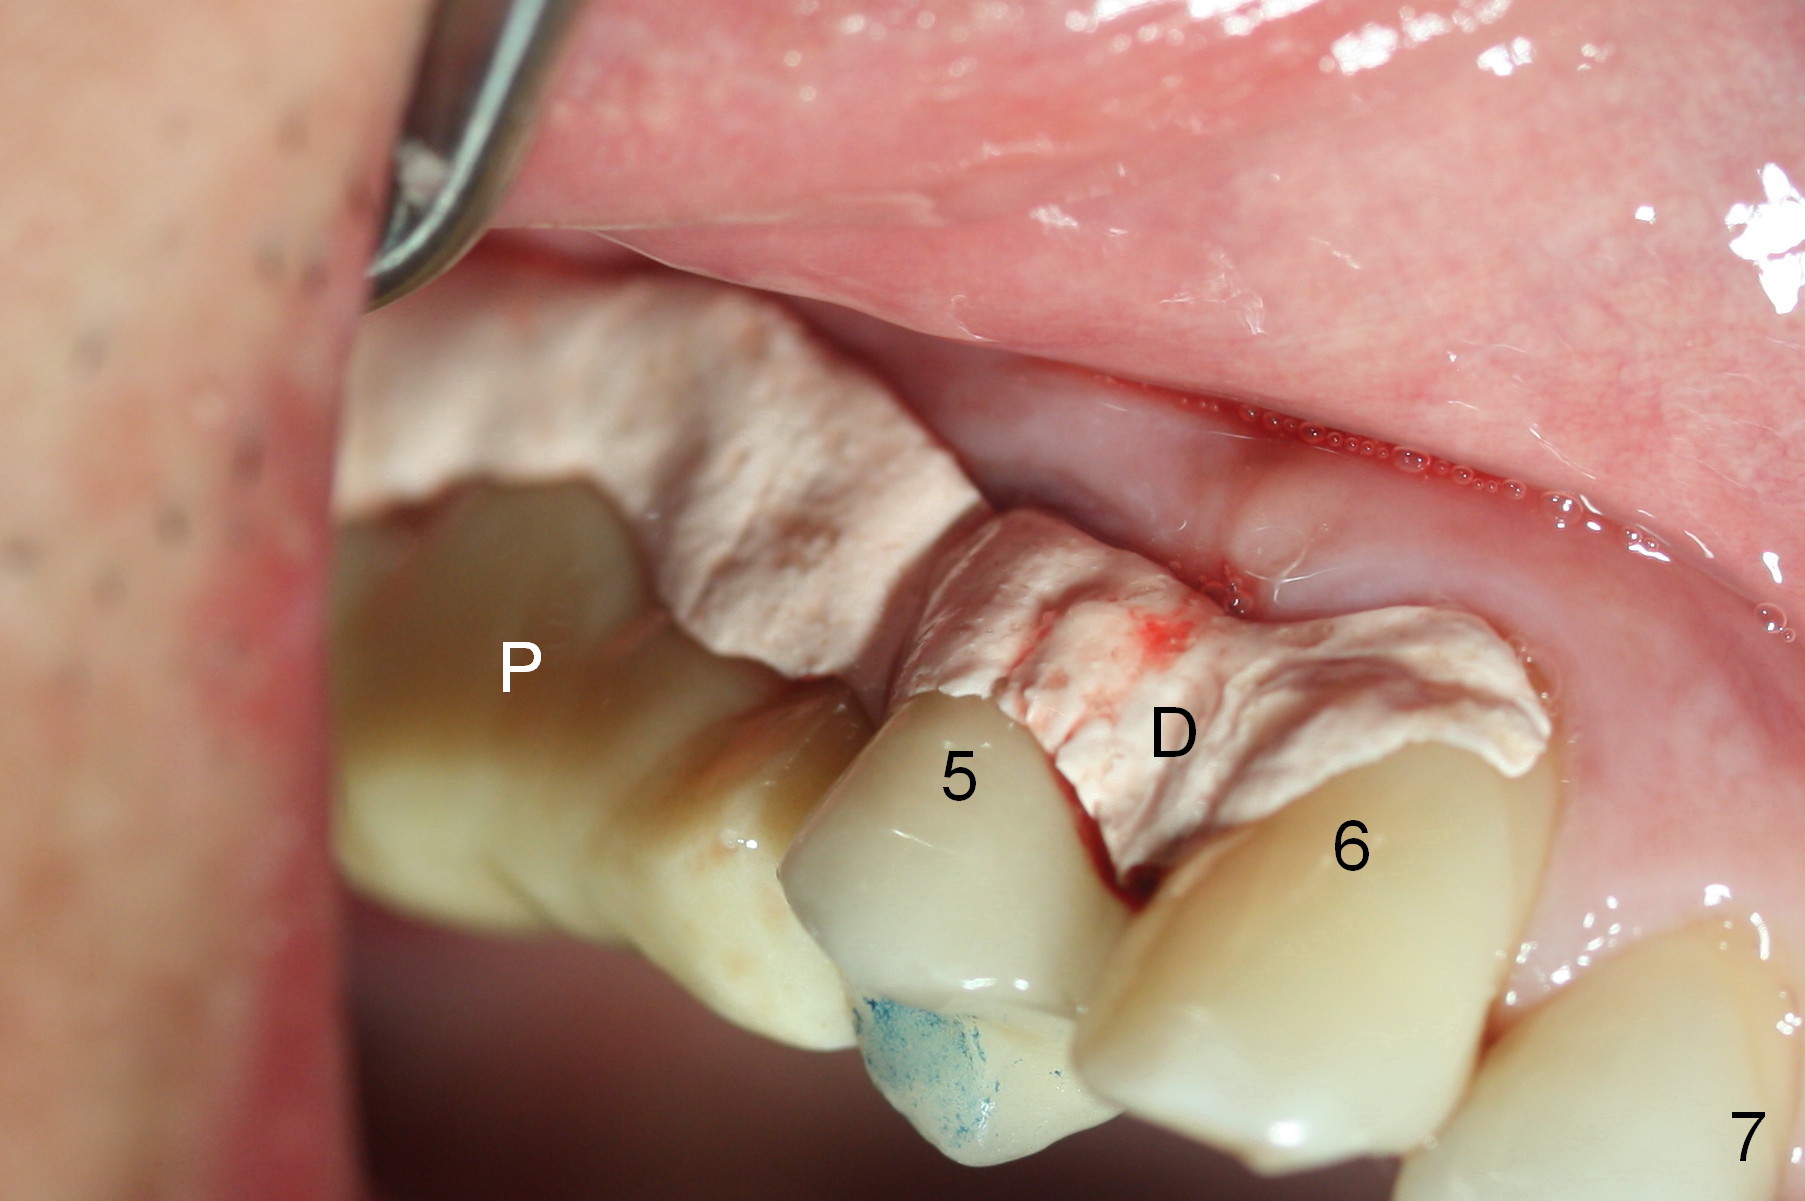

Insertion torque of the three implants is ~ 50 Ncm. Three long (because of severe vertical bone resorption (Fig.1,6)) abutments are placed immediately for immediate splinted provisional (Fig.7,8 P). The latter should have hemostatic effect. Application of peridontal dressing (D) has additional hemostatic function, exerting pressure the most anterior (Fig.7 between the teeth #5,6) and the most posterior (Fig.8 arrow) incision, where the provisional cannot. Sulcus incision is good to remove subgingival calculus. It seems that chronic periodontits and bruxism play roles in pathogenesis of bone loss.